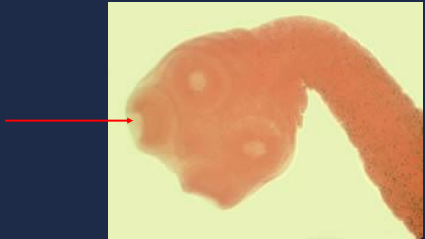

Diphyllobothrium latum

This is a scolex of a _________________.

dorsoventral sucking grooves

What do you call the this part of the *D latum?*